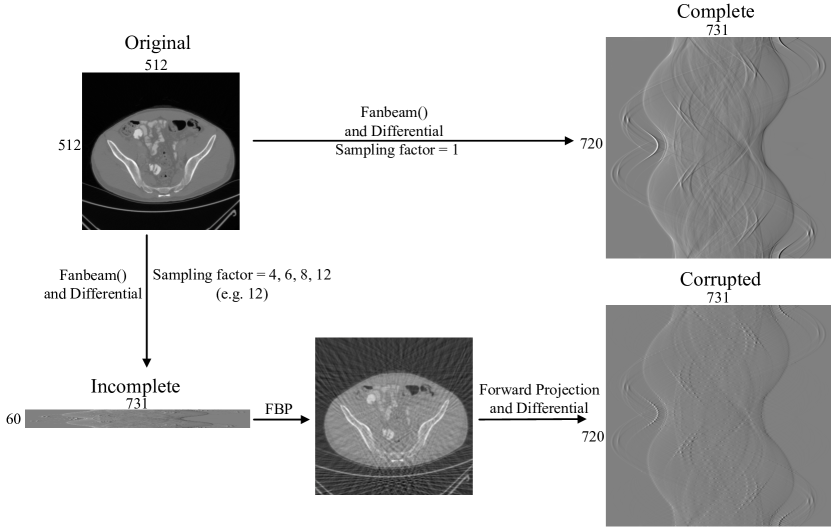

Fig.1 shows the proposed deep learning reconstruction framework for DPC-CT with incomplete projections. It is based on FBP and a neural network and called DLFBP. This framework consists of five parts. Initial FBP reconstruction of the original incomplete phase-contrast sinogram is the first part. The second part is the forward projection operator which is applied to the initial reconstructed image to obtain corrupted sinogram. Then the differential operation is conducted to get differential phase-contrast sinogram. The fourth part is a neural network and used to execute deep learning. Final FBP reconstruction of the complete phase-contrast sinogram from the fourth part is the last part of the framework.

For synthetic data sets, 500 phantoms are used to obtain the fan beam phase-contrast sinograms with different sampling factors. Each phantom consists of tens of ellipses with random refraction coefficients, size, and location. And the sampling factors are set to be 1, 4, 6, 8 and 12. They correspond to 720, 180, 120, 90 and 60 views, respectively. The size of each phantom is pixel. Fan beam sinograms are generated by using the embedded MATLAB function . The width of all the sinograms are 731 pixels. The sinogram with sampling factor 1 has a size pixel and is treated as complete one. Other sinograms are incomplete. Sinograms of 400 phantoms are used to train the framework and those from another 100 phantoms are used to test the framework.

Within the framework, for each incomplete sinogram, the initial FBP reconstruction is firstly executed with Eq.(2) and Eq.(3) to obtain the initial DPC-CT image. Then the forward projection operator in Eq.(4) and the differential method in Eq.(1) are applied to the initial DPC-CT image to generate the corresponding corrupted phase-contrast sinogram with a size pixel. Next the iterative deep learning runs to update the network parameters by making comparison between the corrupted and the complete phase-contrast sinogram.

After that, all the operations and procedures are the same as the ones for synthetic data sets. Fig. 3 is an example of how to prepare the training and testing data.